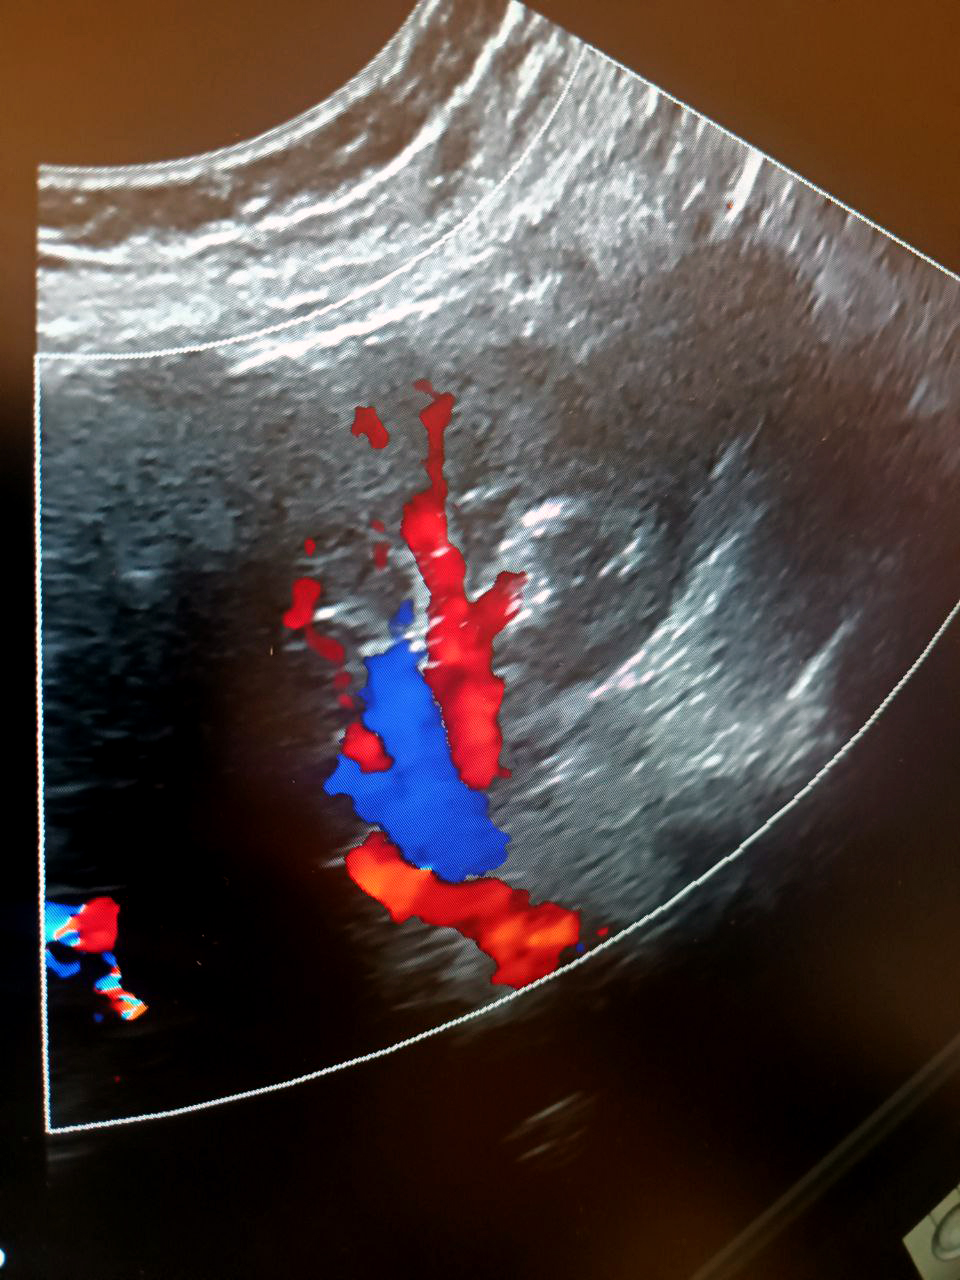

Визуализация сосудов почки.

При ХБП оценка кровотока в родной или трансплантированной почке показывает, насколько работоспособен орган. В первую очередь мы проверяем, нет ли дефицита кровоснабжения, а если есть, выясняем его причины — это могут быть атеросклеротические поражения, вызывающие стенозы (сужения) артерии, перегибы артерии или какие-то иные патологии. Хроническая болезнь почек сопровождается нарушениями на уровне микроциркуляции и коркового слоя, опасные изменения необходимо вовремя отследить. Пересадка почки — сложная операция. Любая операция требует динамического наблюдения, а в данном случае мы должны также оценивать, насколько хорошо приживается трансплантат. В течение первого года после пересадки пациент госпитализируется несколько раз для детального обследования, которое включает обязательную оценку параметров кровотока сосудов почечного трансплантата.